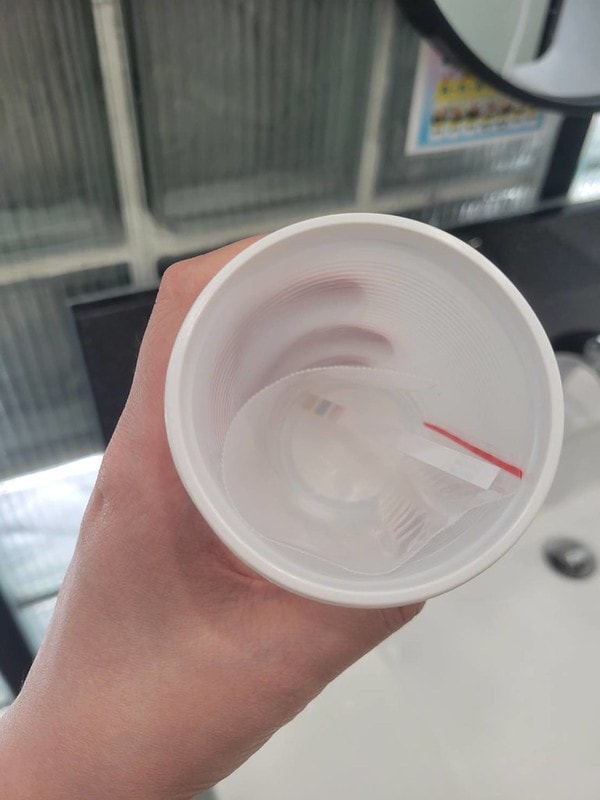

每次產檢都要驗尿~哈哈哈

一開始最前面的話會有個健保給付的檢查報告